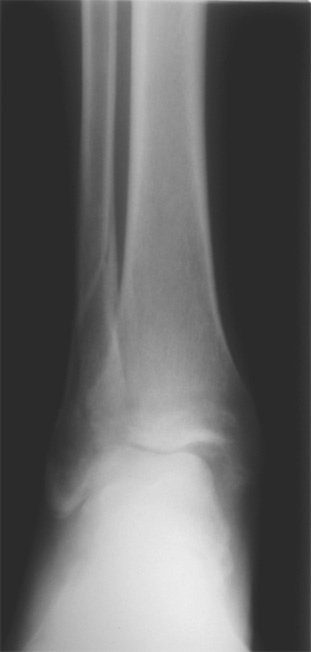

Мне кажется есть все основания попытаться сделать остеосинтез. Боль вследствие нестабильности. Нестабильность вследствие неанатомичного положения дистального отломка малоберцовой кости. Через 1,5 вполне возможно разобщить, репонировать и фиксировать длинный косой перелом наружной лодыжки. Вероятно, одновременно придется делать медиальный доступ для мобилизации внутренней лодыжки. Мы оперируем таких пациентов, функциональные (объем движений) результаты конечно хуже по сравнению с теми кого оперируем в первые 5-10 дней, но вполне удовлетворительные.

Согласен, на предоставленных рентгенограммах все основания для проведения открытого остеосинтеза.

сроки действительно небольшие, но если мы его и возьмем, то пройдет еще минимум неделя, кроме того смущает впечатление сращения н/лодыжки, похоже, что придется не разобщать,а остеотомировать, формирование оссификатов в полости сустава с медиальной стороны, да и сам пациент 1,5 месяца по поводу своей травмы сильно не напрягался